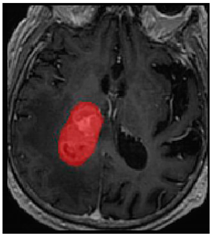

Table 4. Predictions with high dice scores.

Ground truthDeconvNetDeepMedic

Applsci 11 09180 i013 Applsci 11 09180 i014 Applsci 11 09180 i015

PSPNetU-NetV-Net

Applsci 11 09180 i016 Applsci 11 09180 i017 Applsci 11 09180 i018